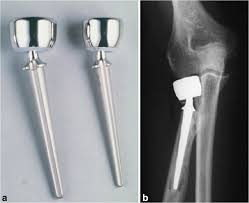

Undergoing arthroplasty for neglected femoral neck fractures at the 359 hospital of the people s liberation. The radial head arthroplasty consisted of first cementing the modular bipolar stem in place. Purpose the goal of arthroplasty is to restore the function of a stiffened joint and relieve pain. Joint resection involves removing a portion of the bone from a stiffened joint.

A bipolar articulation was then inserted and the kinematic pattern defined. Hemi means half and arthroplasty refers to joint replacement replacing the entire hip joint is called. Two types of arthroplastic surgery exist. A monopolar implant was created by placing a circumferential wire around the neck of the bipolar device and tightening it in a way to remove all visual evidence of motion fig.